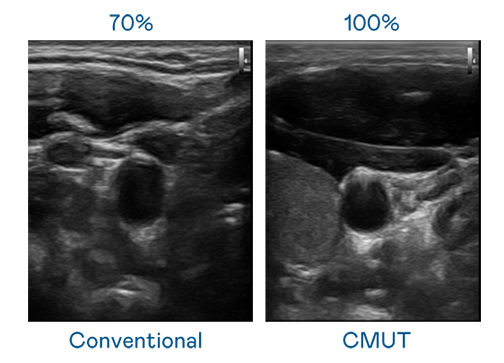

CMUT 技术是一种用电容式微机电元件来产生超音波讯号的技术。与传统 PZT 压电式技术相比,CMUT 频宽增加 30%,更宽频的超音波讯号让影像解析度大幅提升,是实现高影像品质医疗超音波扫描、促进精准医疗发展的关键技术。

大频宽带来超清晰影像

超音波影像的解析度高低,首先取决于探头能发出的讯号频宽。贴身情人之贴身恋国语 CMUT 可提供高清晰的超音波讯号,提供高频宽、高灵敏度、影像纹理细节更高的超音波影像,协助医护人员缩短影像判读时间及利用精准的医疗影像进行诊断。